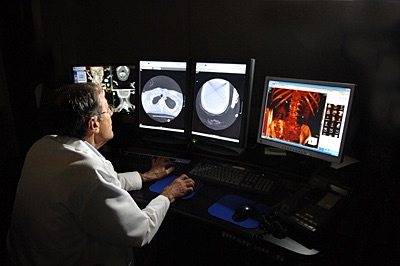

Because when someone is wheeled into the trauma bay, their next destination may be the CT scanner to determine the extent of their injury.

Or the surgical theater as a last-ditch effort to save their nearly life-less body.